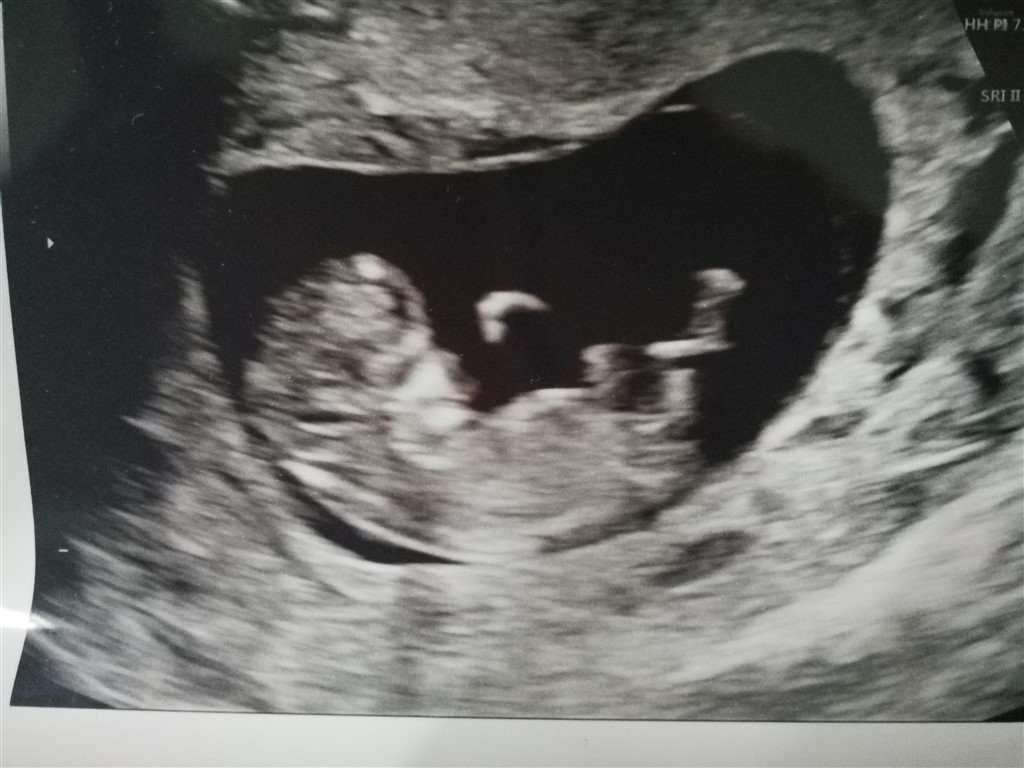

Var til nf i går og så en meget livlig baby, så livlig så det næsten var svært at få billeder. Det var et vildt syn! Blev så lige sat en uge tilbage så er kun 11+3 idag.

Vedhæftede fotos (klik for at se i fuld størrelse)